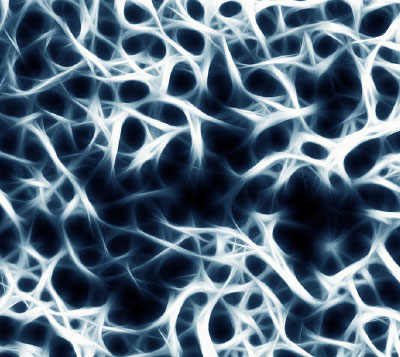

Knochendichtemessung

Diese Untersuchung misst den Mineralsalzgehalt des Knochens. Von der Knochendichte hängt ab, wie bruchfest ein Knochen ist. Die Knochendichtemessung wird vor allem bei Verdacht auf Osteoporose (Knochenschwund) durchgeführt, zum Beispiel bei Frauen nach den Wechseljahren oder Männern mit erhöhtem Osteoporose-Risiko (Alkohol-, Nikotinmissbrauch, vererbte Veranlagung, Diabetikern oder Mangelernährung) oder nach Knochenbrüchen ohne adäquates Trauma.

Wir arbeiten in unserer Praxis mit der Zweispektren-Röntgenabsorptiometrie (DXA/DEXA), ein empfohlenes Standardverfahren zur Knochendichtemessung. Dabei wird das Hüftgelenk und die Lendenwirbelsäule geröntgt. Die Untersuchung macht bei geringer Strahlenbelastung schon kleine Veränderungen der Knochendichte sichtbar und ist insbesondere zur Verlaufsbeobachtung von großem Nutzen, um über den Einsatz knochenstoffwechselfördernder Medikamente zu entscheiden.